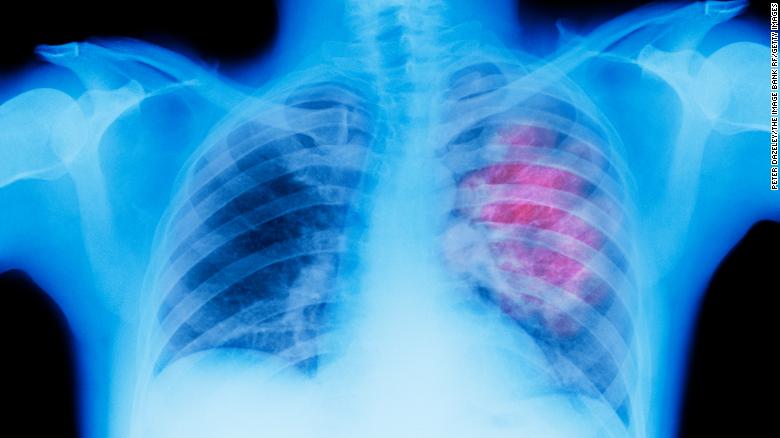

| In 2020, cancer was the second leading cause of death, after heart disease, in the United States. A new study finds that nearly half of all cancer deaths worldwide can be attributed to preventable risk factors, including the three leading risks: smoking, drinking too much alcohol, or having a high body mass index. Published in the Lancet last week, the study finds in 2019 that 44% of all cancer deaths and 42% of the healthy years lost from cancer are related to these kinds of risks. Researchers from the Institute for Health Metrics and Evaluation at the University of Washington, zeroed in on cancer deaths and disability from 2010 to 2019 across 204 countries, examining 23 cancer types and 34 risk factors. The researchers found the leading cancers in terms of risk-attributable deaths globally in 2019 were tracheal, bronchus and lung cancer for both men and women. Also concerning: risk-attributable cancer deaths are on the rise, increasing worldwide by 20.4% from 2010 to 2019. The new study "clearly delineates" the importance of primary cancer prevention and "the increasing cancer numbers related to obesity clearly demands our attention," said Dr. William Dahut, chief scientific officer for the American Cancer Society, who was not involved in the new study. "Modifying behavior could lead to millions more lives saved, greatly overshadowing the impact of any drug ever approved," he added. "The continued impact of tobacco despite approximately 65 years of a linkage to cancer remains very problematic." It is definitely striking news, but I'm also optimistic because it is a trend that we can change. An accompanying editorial noted that many of these risk factors can be associated with poverty. "Poverty influences the environments in which people live, and those environments shape the lifestyle decisions that people are able to make. Action to prevent cancer requires concerted effort within and outside the health sector. This action includes specific policies focused on reducing exposure to cancer-causing risk factors, such as tobacco and alcohol use, and access to vaccinations that prevent cancer-causing infections, including hepatitis B and HPV," the editorial said. Some of the changes that need to happen are at an institutional level, but there are also actions we can take on ourselves. We can eat better and move more. We can work with our doctors to drink and smoke less. These steps can improve our own health, but the overall health of the world, too. | |